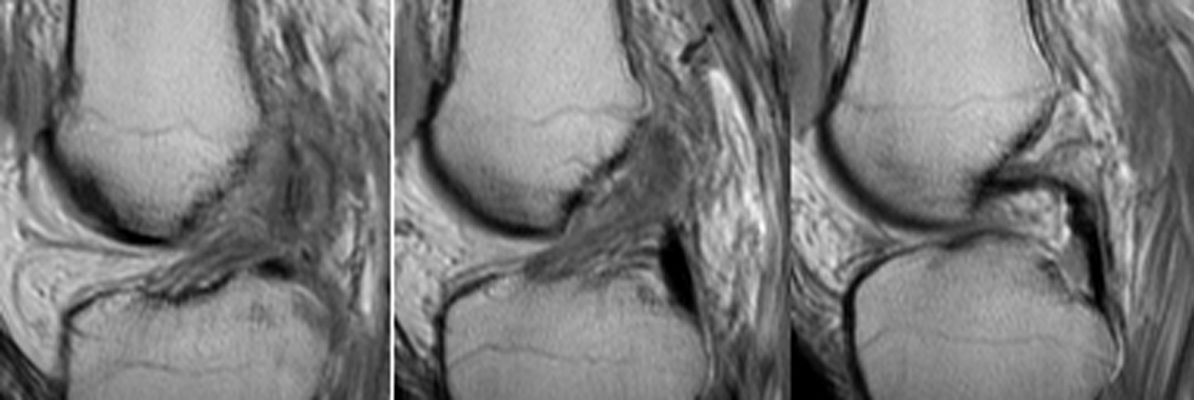

Return to Segond Fracture